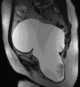

Cyst containing debris

Pilonidal disease is a type of skin infection which typically occurs as a cyst between the cheeks of the buttocks and often at the upper end. Symptoms may include pain, swelling, and redness. [Source: Wikipedia ]